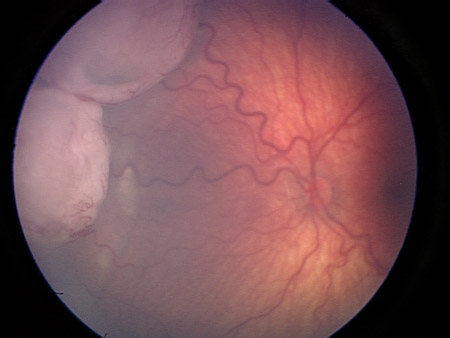

Large retinoblastoma focus in the left eye

Personal collection of Dr Timothy Murray